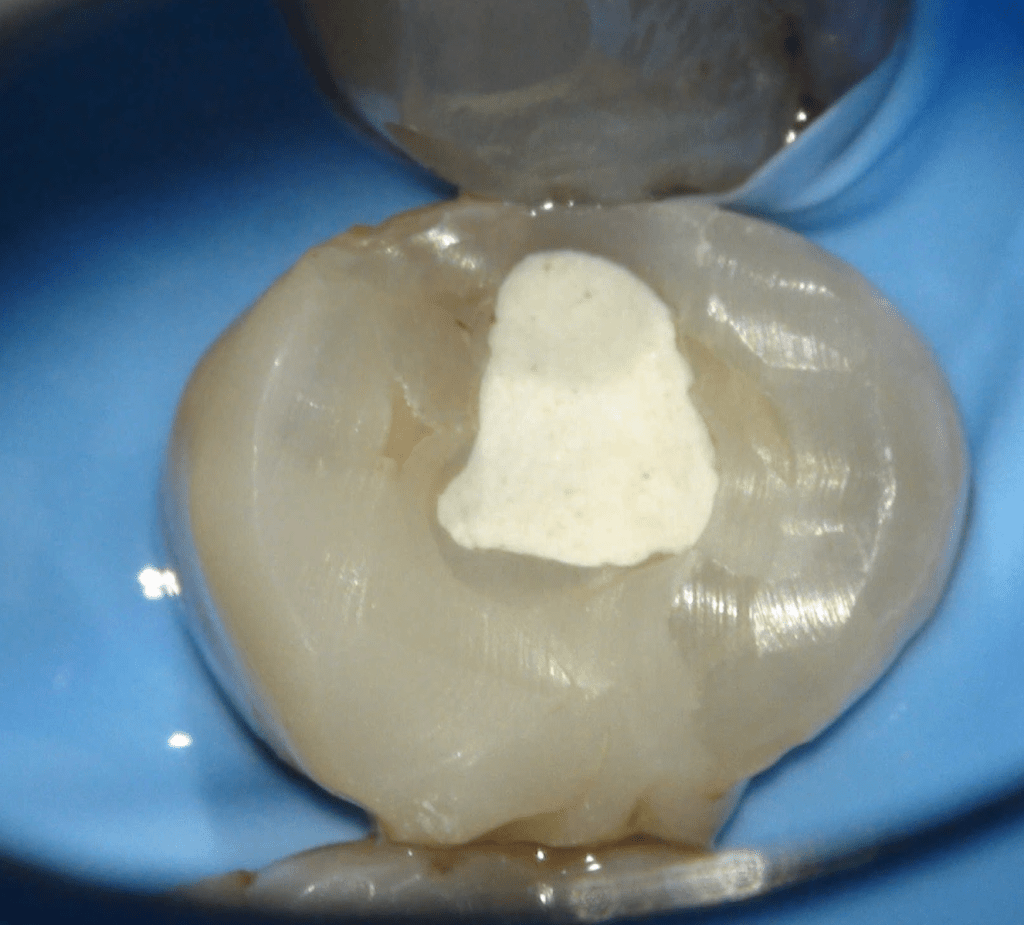

Fisura, remoción amalgama para explorar